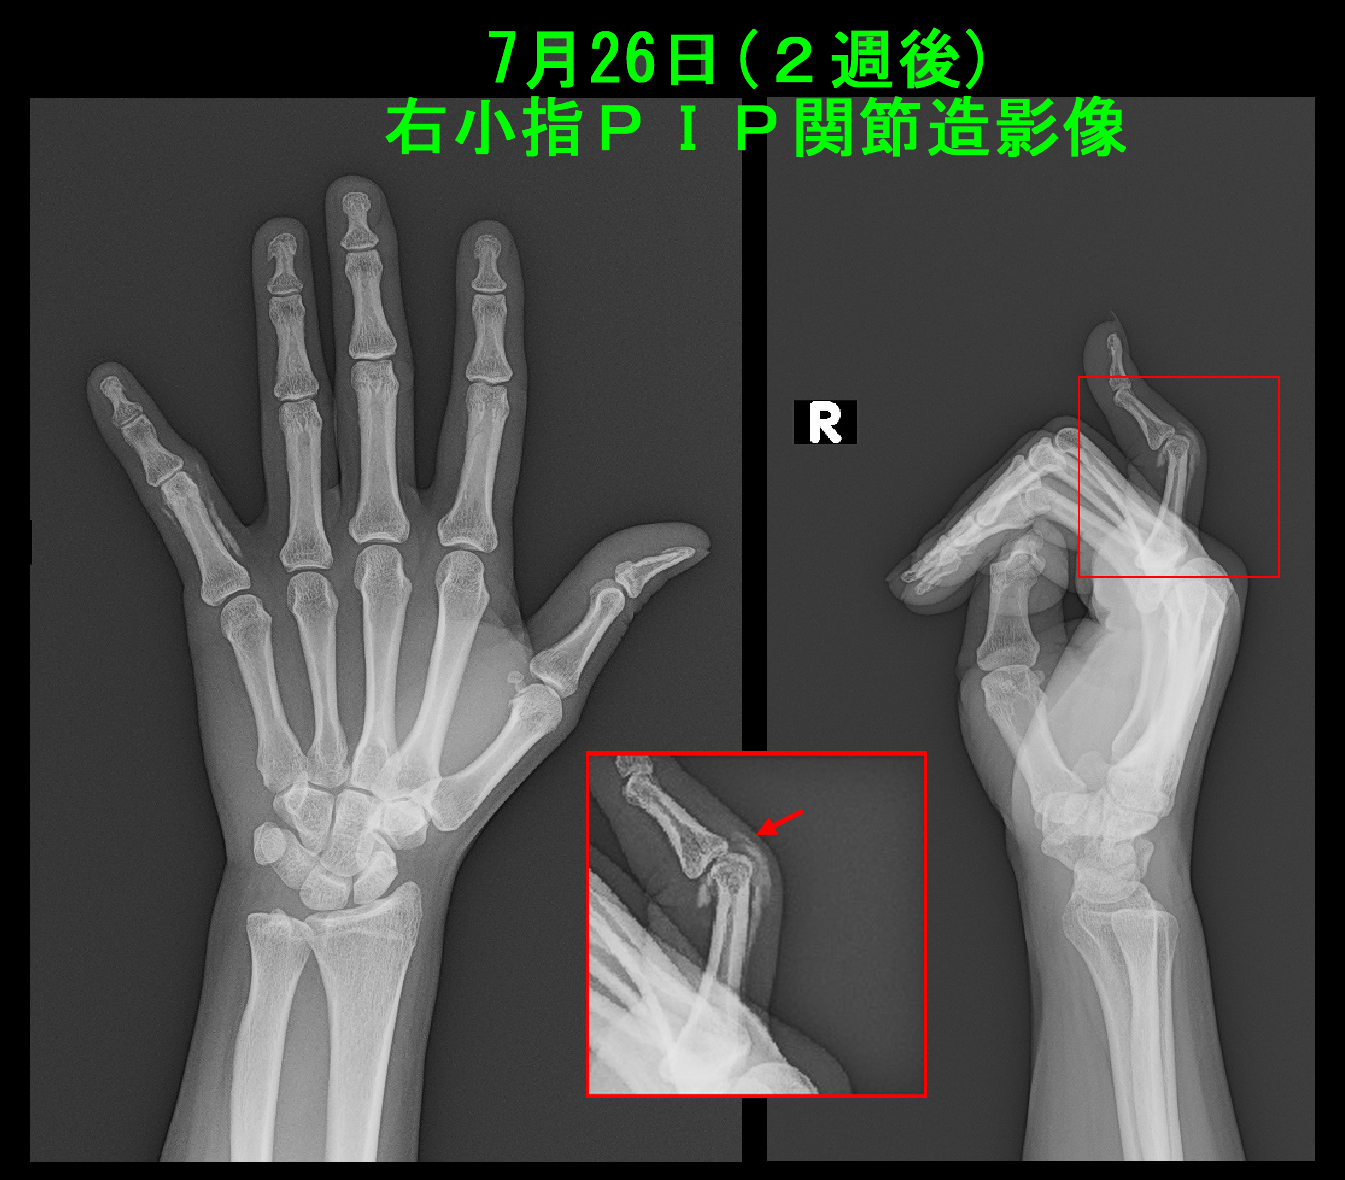

2週後の7月26日には仕事で邪魔だと固定のアルミシーネを除去して受診されました。ボタン穴変形が発生しています。このままでは変形が固定する(生涯変形が残る)可能性が高いことを説明し、関節の腫脹を軽減させるために関節内注射を行っています。ここからは小指単独の固定としました。

41才女 Xp2.jpg

このPIP関節造影レントゲン像で(赤矢印)伸筋腱は断裂していないことが確認されました。